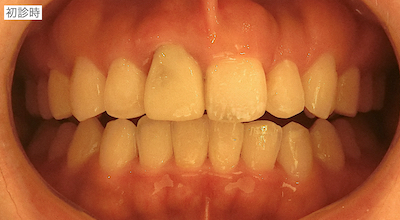

京都 四条烏丸の歯科医院 RIMO dental clinicの院長 小川智功です。

コンポジットレジンで歯冠部が作られていました。歯肉縁下まで及んでいたので、いったん全て外して、状況を確認した方が良いことを説明しました。患者さんも歯肉のラインが気になっておられ、前歯の形も理想ではないとのことだったので、全て外して仮歯の作成を行うことを説明し、同意頂けました。

旧仮歯を撤去したところ、歯根が一部水平的に破折していました。歯肉のラインが歪になっていたのはこのことが原因であったと説明しました。支台築造を行い、仮歯を作成しました。患者さんはホワイトニングを希望しておられたので、ホームホワイトニングを行ったのちに周りの歯の色に合わせてセラミック冠を作成することで同意頂いたので、ホームホワイトニングを行いました。